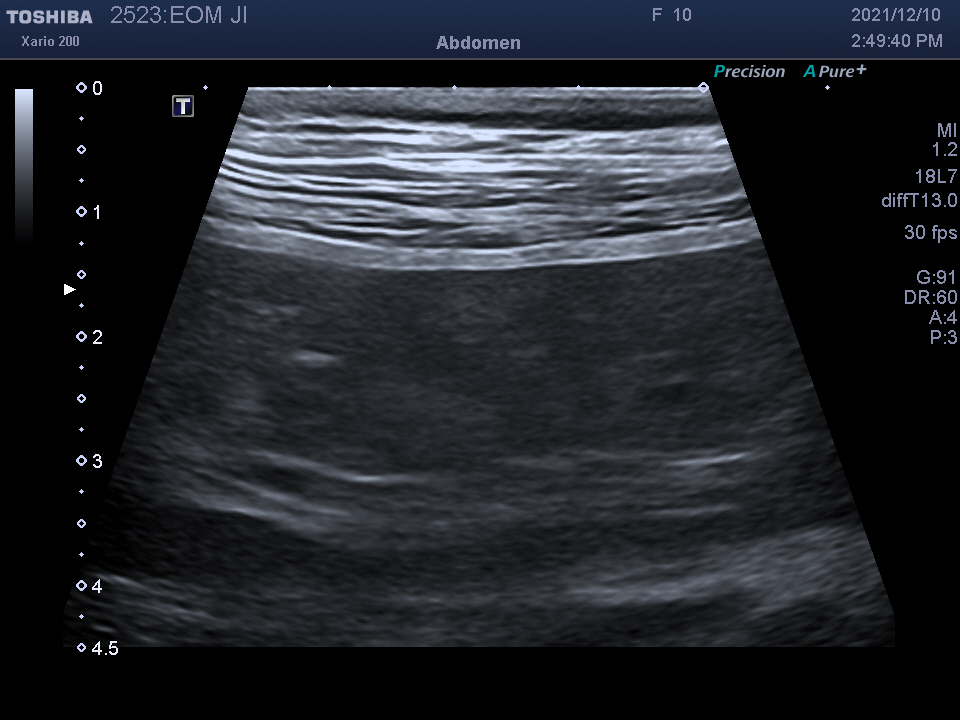

복강 내 장기를 자세히 알 수 있는

복부 초음파 검사를 진행하였습니다.

검사 결과를 종합하여 자궁 축농증이라는 진단을 받았습니다.